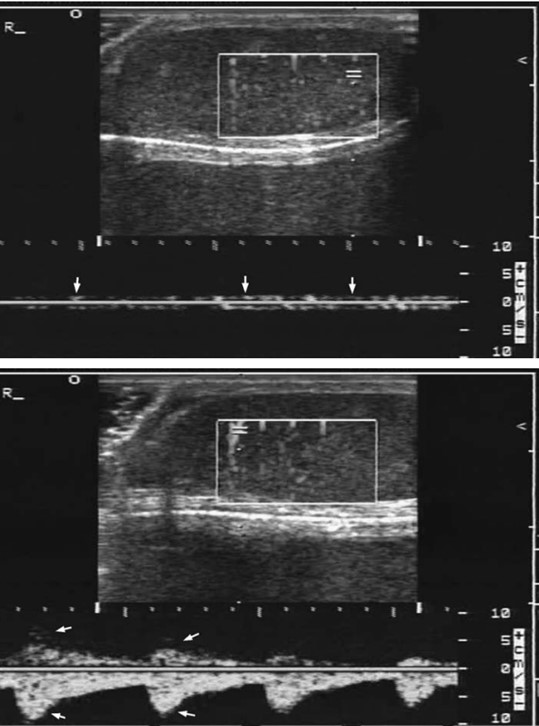

Arterial waveform resistive index (RI) is one of the most sensitive and specific tests for testicular torsion. The RI is calculated when an arterial waveform is identified (arterial has prominent pulsations compared to the more flat and unchanging venous waveform), and a pulse wave Doppler tracing shows peak systolic velocity and lowest diastolic velocity. The formula for calculating this is noted in Figure 1 and an example waveform in Figure 2. A normal RI is 0.5-0.7. Echogenicity of the testicle also changes over time as parenchymal bleeding builds, causing increased brightness on the affected side. As this bleeding occurs sporadically, the echotexture becomes increasingly varied, causing heterogeneous echogenicity.

Figure 1. Resistive index formula for arterial waveforms

Figure 2. Examples of a normal testicular venous waveform (upper panel) and an arterial waveform (lower panel)10